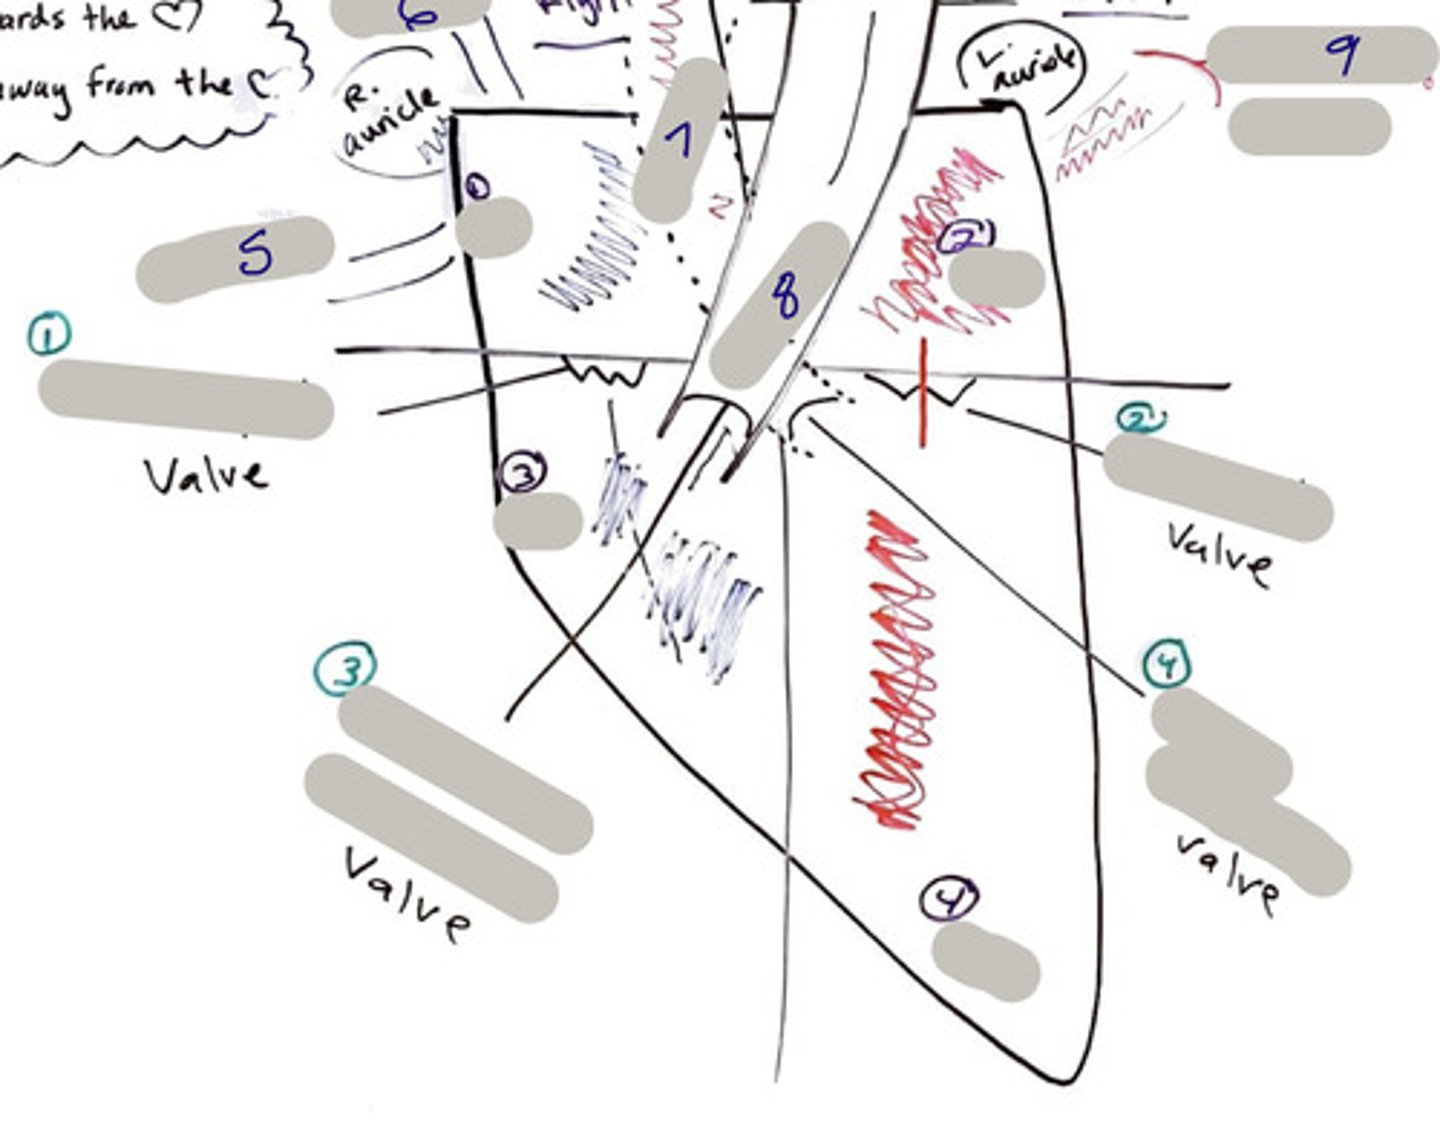

Tricuspid Valve (Right Atrioventricular Valve)

1-valve

Bicuspid valve (Left Atrioventricular Valve)

2-valve

Pulmonary Semilunar Valve

3-valve

Aortic Semilunar Valve

4-valve

Right Atrium

1-chamber

Left Atrium

2-chamber

Right Ventricle

3-chamber

Left Ventricle

4-chamber

Inferior Vena Cava

5-A vein that is the largest vein in the human body and returns blood to the right atrium of the heart from bodily parts below the diaphragm.

Superior Vena Cava

6-A vein that is the second largest vein in the human body and returns blood to the right atrium of the heart from the upper half of the body.

Aorta

7-The large arterial trunk that carries blood from the heart to be distributed by branch arteries through the body.

Pulmonary Trunk

8-carries blood from right ventricle to pulmonary arteries

Pulmonary veins

9-a vein carrying oxygenated blood from the lungs to the left atrium of the heart.